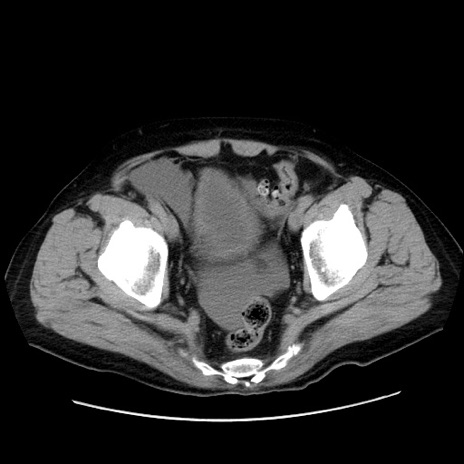

症例30(横断像)

【症例】80歳代男性

【主訴】臍周囲痛

【現病歴】約6時間前から臍下部痛が出現。次第に腹部膨隆・背部痛も生じてきたため来院。背部痛の場所は変化しない。

【身体所見】意識清明、BT 36.3℃、BP  131/87mmHg、P 87bpm、SpO2 100%(RA)、臍周囲自発痛・圧痛あり、反跳痛なし、自発痛部位に一致して板状硬あり、腹部膨隆、腸雑音減弱、CVA tenderness両側陰性。